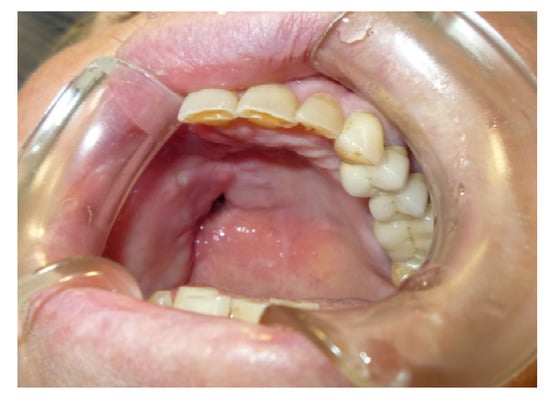

3.1.4. Case 4: P.M.A.

| P.M.A | X | * | 5 | 5 |